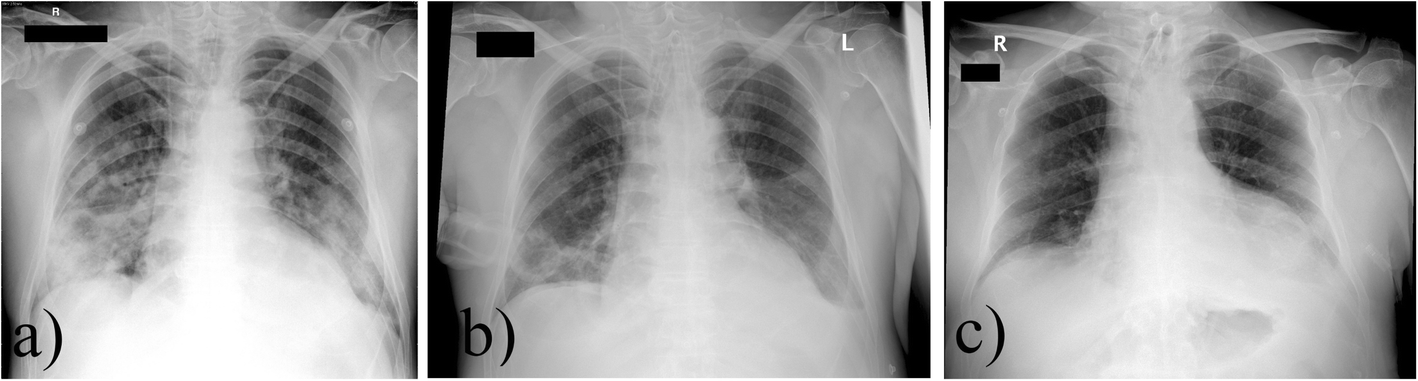

Fig. 1

From: Successful management of zinc phosphide poisoning—a Hungarian case

Anteroposterior chest X-rays of the patient on day 1 (a), 7 (b), 15 (c). a Day 1, confluent atelectasis on the day of admission. Central venous cannula and endotracheal tube in correct position. b Day 7, control examination. No signs of consolidation or atelectasis. c Day 15, control examination. No signs of consolidation or atelectasis. Tracheostomy tube in control position